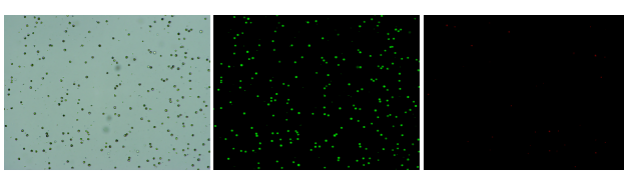

人膽管癌樣本,活性90.45%,結團率7.2%